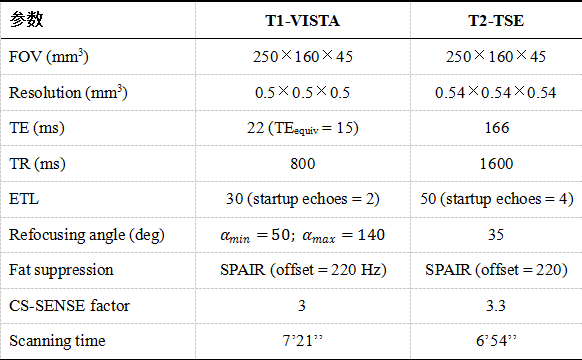

本研究序列调测的所有磁共振实验均在清华大学生物医学影像中心的一台3.0T磁共振扫描仪(Ingenia, Philips Healthcare, The Netherlands)上进行,使用配套的32通道头线圈及8通道颈动脉线圈进行成像。颅内外大范围动脉管壁T1及T2加权成像均采用黑血快速自旋回波成像(Turbo Spin-Echo, TSE)序列实现,成像范围包含大脑中动脉及全部颈动脉(FOV = 250×160×45 mm3),T1加权序列空间分辨率为各向同性0.5 mm,T2加权序列为各向同性0.54 mm。其中T1加权成像使用变角度的快速自旋回波成像(Variable Flip Angle Turbo Spin-Echo, VFA-TSE; VISTA, Philips Healthcare)缩短TEequiv值从而得到更纯的T1对比度,同时增强黑血效应。两序列均采用谱衰减反转脉冲(Spectral Attenuated Inversion Recovery, SPAIR)进行脂肪抑制,从而得到更清晰的外管壁轮廓。两个序列均采用压缩感知算法对成像环节进行加速,使得T1加权成像序列扫描时间缩短至7’21’’,T2加权成像序列至6’54’’。两序列详细参数见表1,成像效果示意图见图1、图2。

表1 颅内外大范围高分辨率动脉管壁T1、T2加权成像序列参数